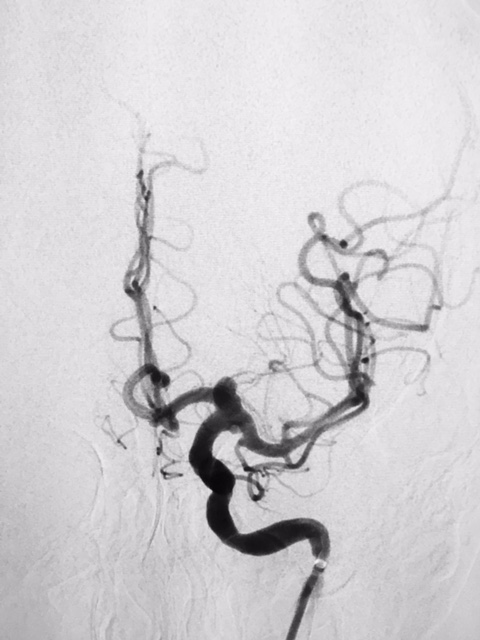

Aneurisma de topo da carótida

SNA. 76 anos . Durante investigação ambulatorial de cefaléia e tremor nas mãos foi realizado Angiotomografia de crânio evidenciando aneurisma incidental em topo da...